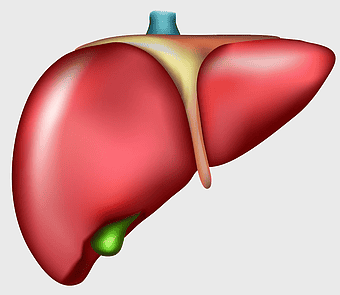

liver with gallbladder diagram, human liver function, bile production organ illustration, digestive system anatomy, liver and bile duct visual, human anatomy medical graphic, hepatology reference image -

human liver model, liver organ cirrhosis drawing, medical anatomy illustration, red liver organ, bile duct structure, hepatic lobe depiction, digestive system organ -